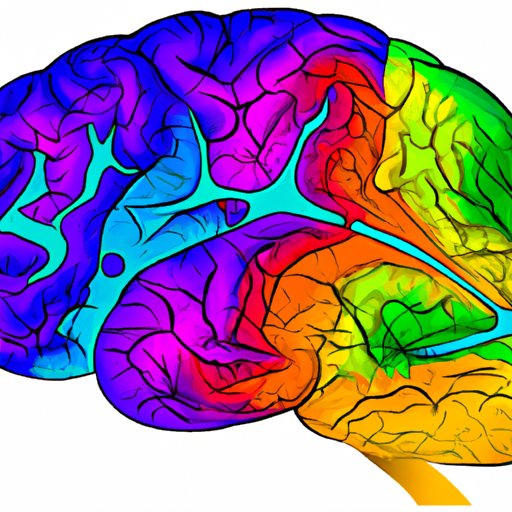

The purpose of this article is to explore how psilocin works in the brain. We will examine the neurochemical effects of the compound on the brain and investigate the neural pathways it activates. We will also analyze the neurophysiological and brain imaging effects of psilocin.

In order to understand how psilocin affects the brain, we must first examine the neural pathways it activates. Psilocin binds to serotonin receptors located in the prefrontal cortex, which is the part of the brain responsible for higher-order cognition and decision-making. When psilocin binds to these receptors, it disrupts the normal flow of information between neurons, leading to altered perceptions, emotions, and thoughts.

Psilocin also affects the thalamus, which is responsible for relaying sensory information to the cerebral cortex. When psilocin binds to serotonin receptors in the thalamus, it can lead to heightened sensory awareness and an increased sensitivity to light, sound, and touch.

The hippocampus, a region of the brain involved in memory formation and retrieval, is also impacted by psilocin. When psilocin binds to serotonin receptors in the hippocampus, it can lead to enhanced recollection of past experiences and heightened creativity.

Finally, psilocin can affect the ventral tegmental area (VTA) of the brain, which is associated with reward and motivation. When psilocin binds to serotonin receptors in the VTA, it can lead to feelings of euphoria and a sense of connection to others.

In addition to the neural pathways it activates, psilocin also produces neurophysiological changes in the brain. Studies have shown that psilocin can reduce blood flow and electrical activity in certain regions of the brain, including the prefrontal cortex and cerebellum. This decreased activity is thought to be responsible for the dream-like state and altered time perception associated with psilocin use.

Brain imaging studies have revealed that psilocin can produce significant changes in the activity of the brain. In particular, psilocin has been shown to decrease activity in the default mode network (DMN), a network of brain regions associated with self-reflection and introspection. This decreased activity is thought to be responsible for the feeling of ego dissolution often experienced during a psychedelic experience.